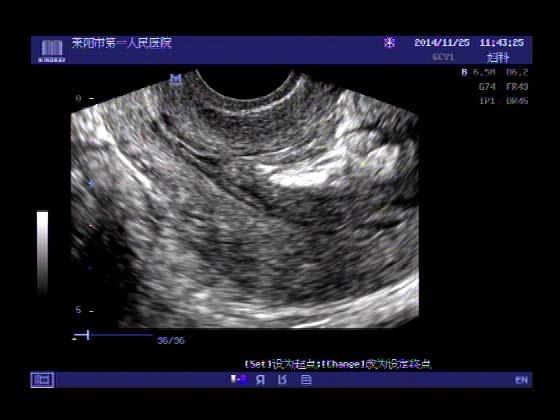

超声入门贴379---------粘膜下肌瘤(阴超的魅力)

女,43岁,月经量多3个多月,加重一个月

外院彩超检查提示:子宫后肌壁略高回声团------肌瘤?息肉?,盆腔少量积液

今天来我院检查:

巧妇难为无米之炊,经腹部超声确实很难定,阴超一目了然,乡镇医院诊断水平的提高更迫切的需要高档仪器的引进!